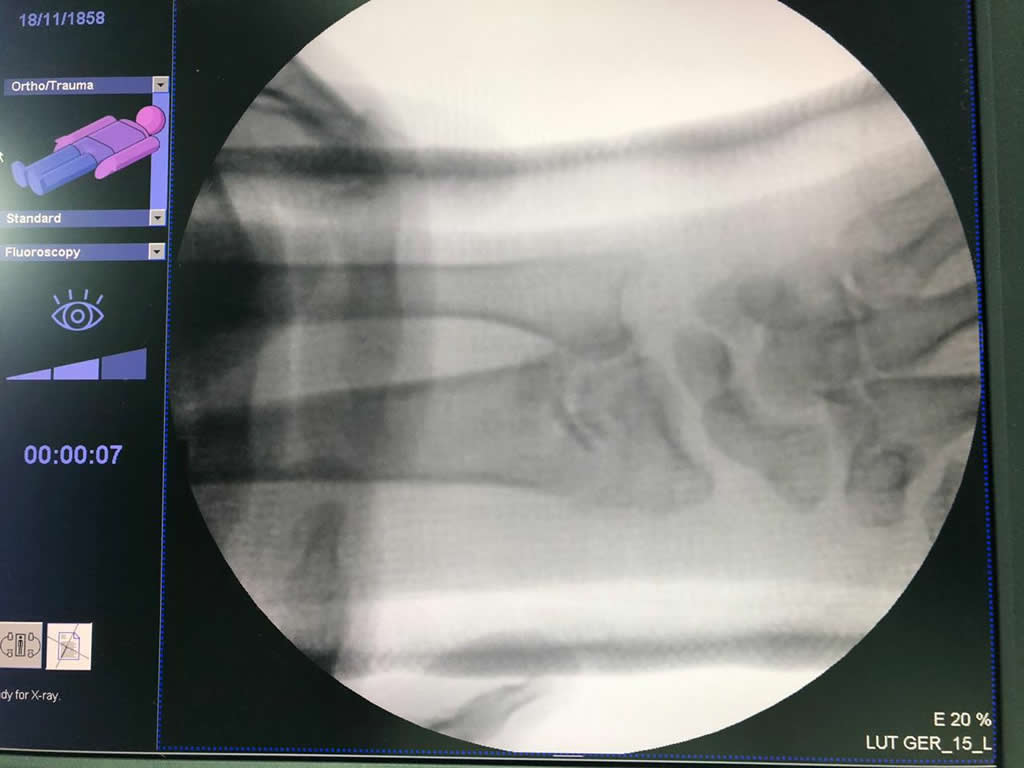

Los procedimientos más comunes en cirugía de la mano son aquellos destinados a reparar traumatismos, incluyendo lesiones de tendones, nervios, vasos sanguíneos, y articulaciones; huesos fracturados; y quemaduras, cortes, y otros daños de la piel.